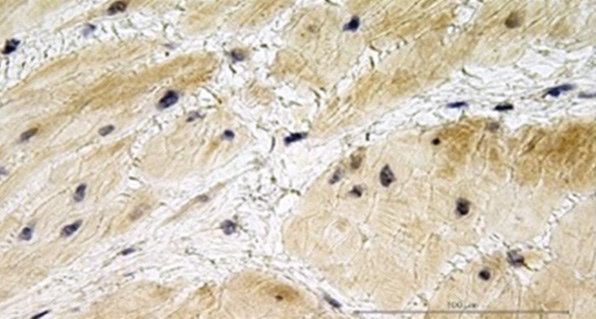

Для оценки результатов иммуногистохимического исследования миометрия выполнена цифровая микроскопия и проанализировано 695 микрофотографий. Экспрессия изучаемых факторов в исследуемых группах представлена в табл. 5.

Таблица 5. Экспрессия провоспалительного белка матриксной металлопротеиназы-2 и тканевых ингибиторов металлопротеиназ-1 и -2 в миометрии исследуемых групп

Table 5. Expression of the pro-inflammatory protein matrix metalloproteinase-2 and tissue inhibitors of metalloproteinases 1 and 2 in the myometrium of patients in the study groups

Группа | Экспрессия ММР-2 | Экспрессия TIМР-1 | Экспрессия TIМР-2 |

1 | |||

2 | |||

3 |

Примечание. Иммуногистохимическое исследование, увеличение ×200. MMP-2 — матриксная металлопротеиназа-2; TIMP-1, -2 — тканевые ингибиторы металлопротеиназ-1 и -2.